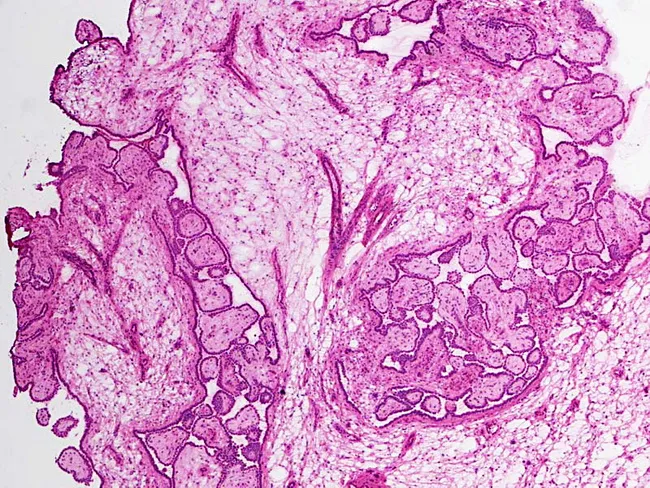

However, the definitive diagnosis always requires a biopsy. This procedure involves taking a small tissue sample from the affected omentum or peritoneum, which is then examined by a pathologist under a microscope. This examination confirms the presence of mesothelioma cells and helps determine the specific cell type, which is vital for guiding treatment.